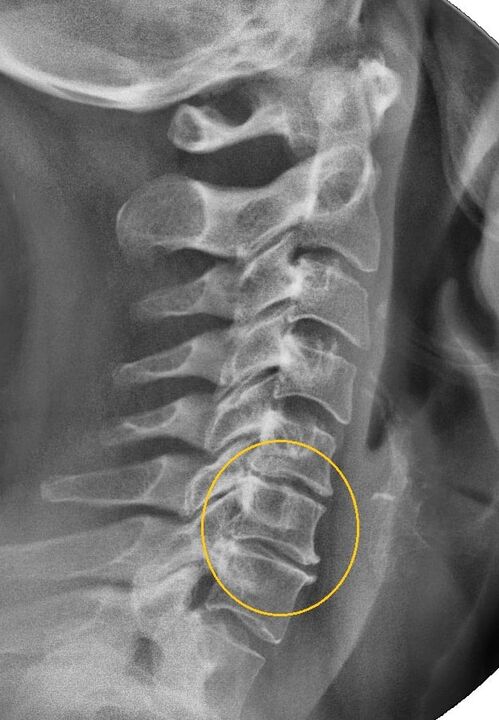

The most informative diagnostic procedure is radiography.Grade 1 pathology corresponds to grade 1 or 2 radiological stage.The resulting images visualize the typical symptoms of the disease.

| X-ray staging of grade 1 cervical osteochondrosis | Feature flag |

|---|---|

| first stage | Small changes in the curvature of the spine in the neck, affecting one or more segments |

| second stage | Slight thickening of the intervertebral discs, deformation of the uncinus, straightening of the lordosis, and slight growth of the bone structure |